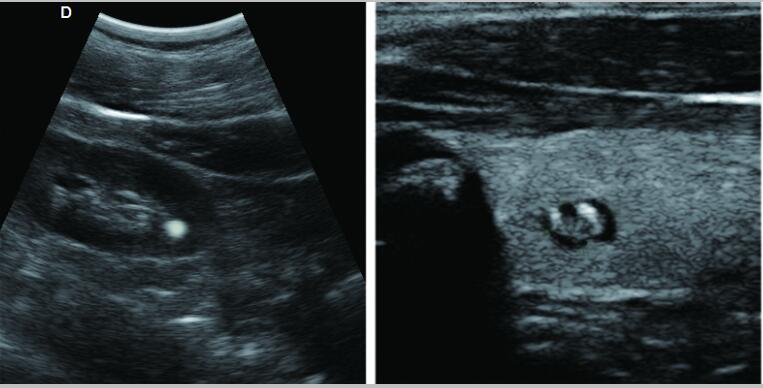

7.應(yīng)用:腹部、婦科、產(chǎn)科、心臟、血管和小器官、泌尿科、肌肉骨骼、兒科等